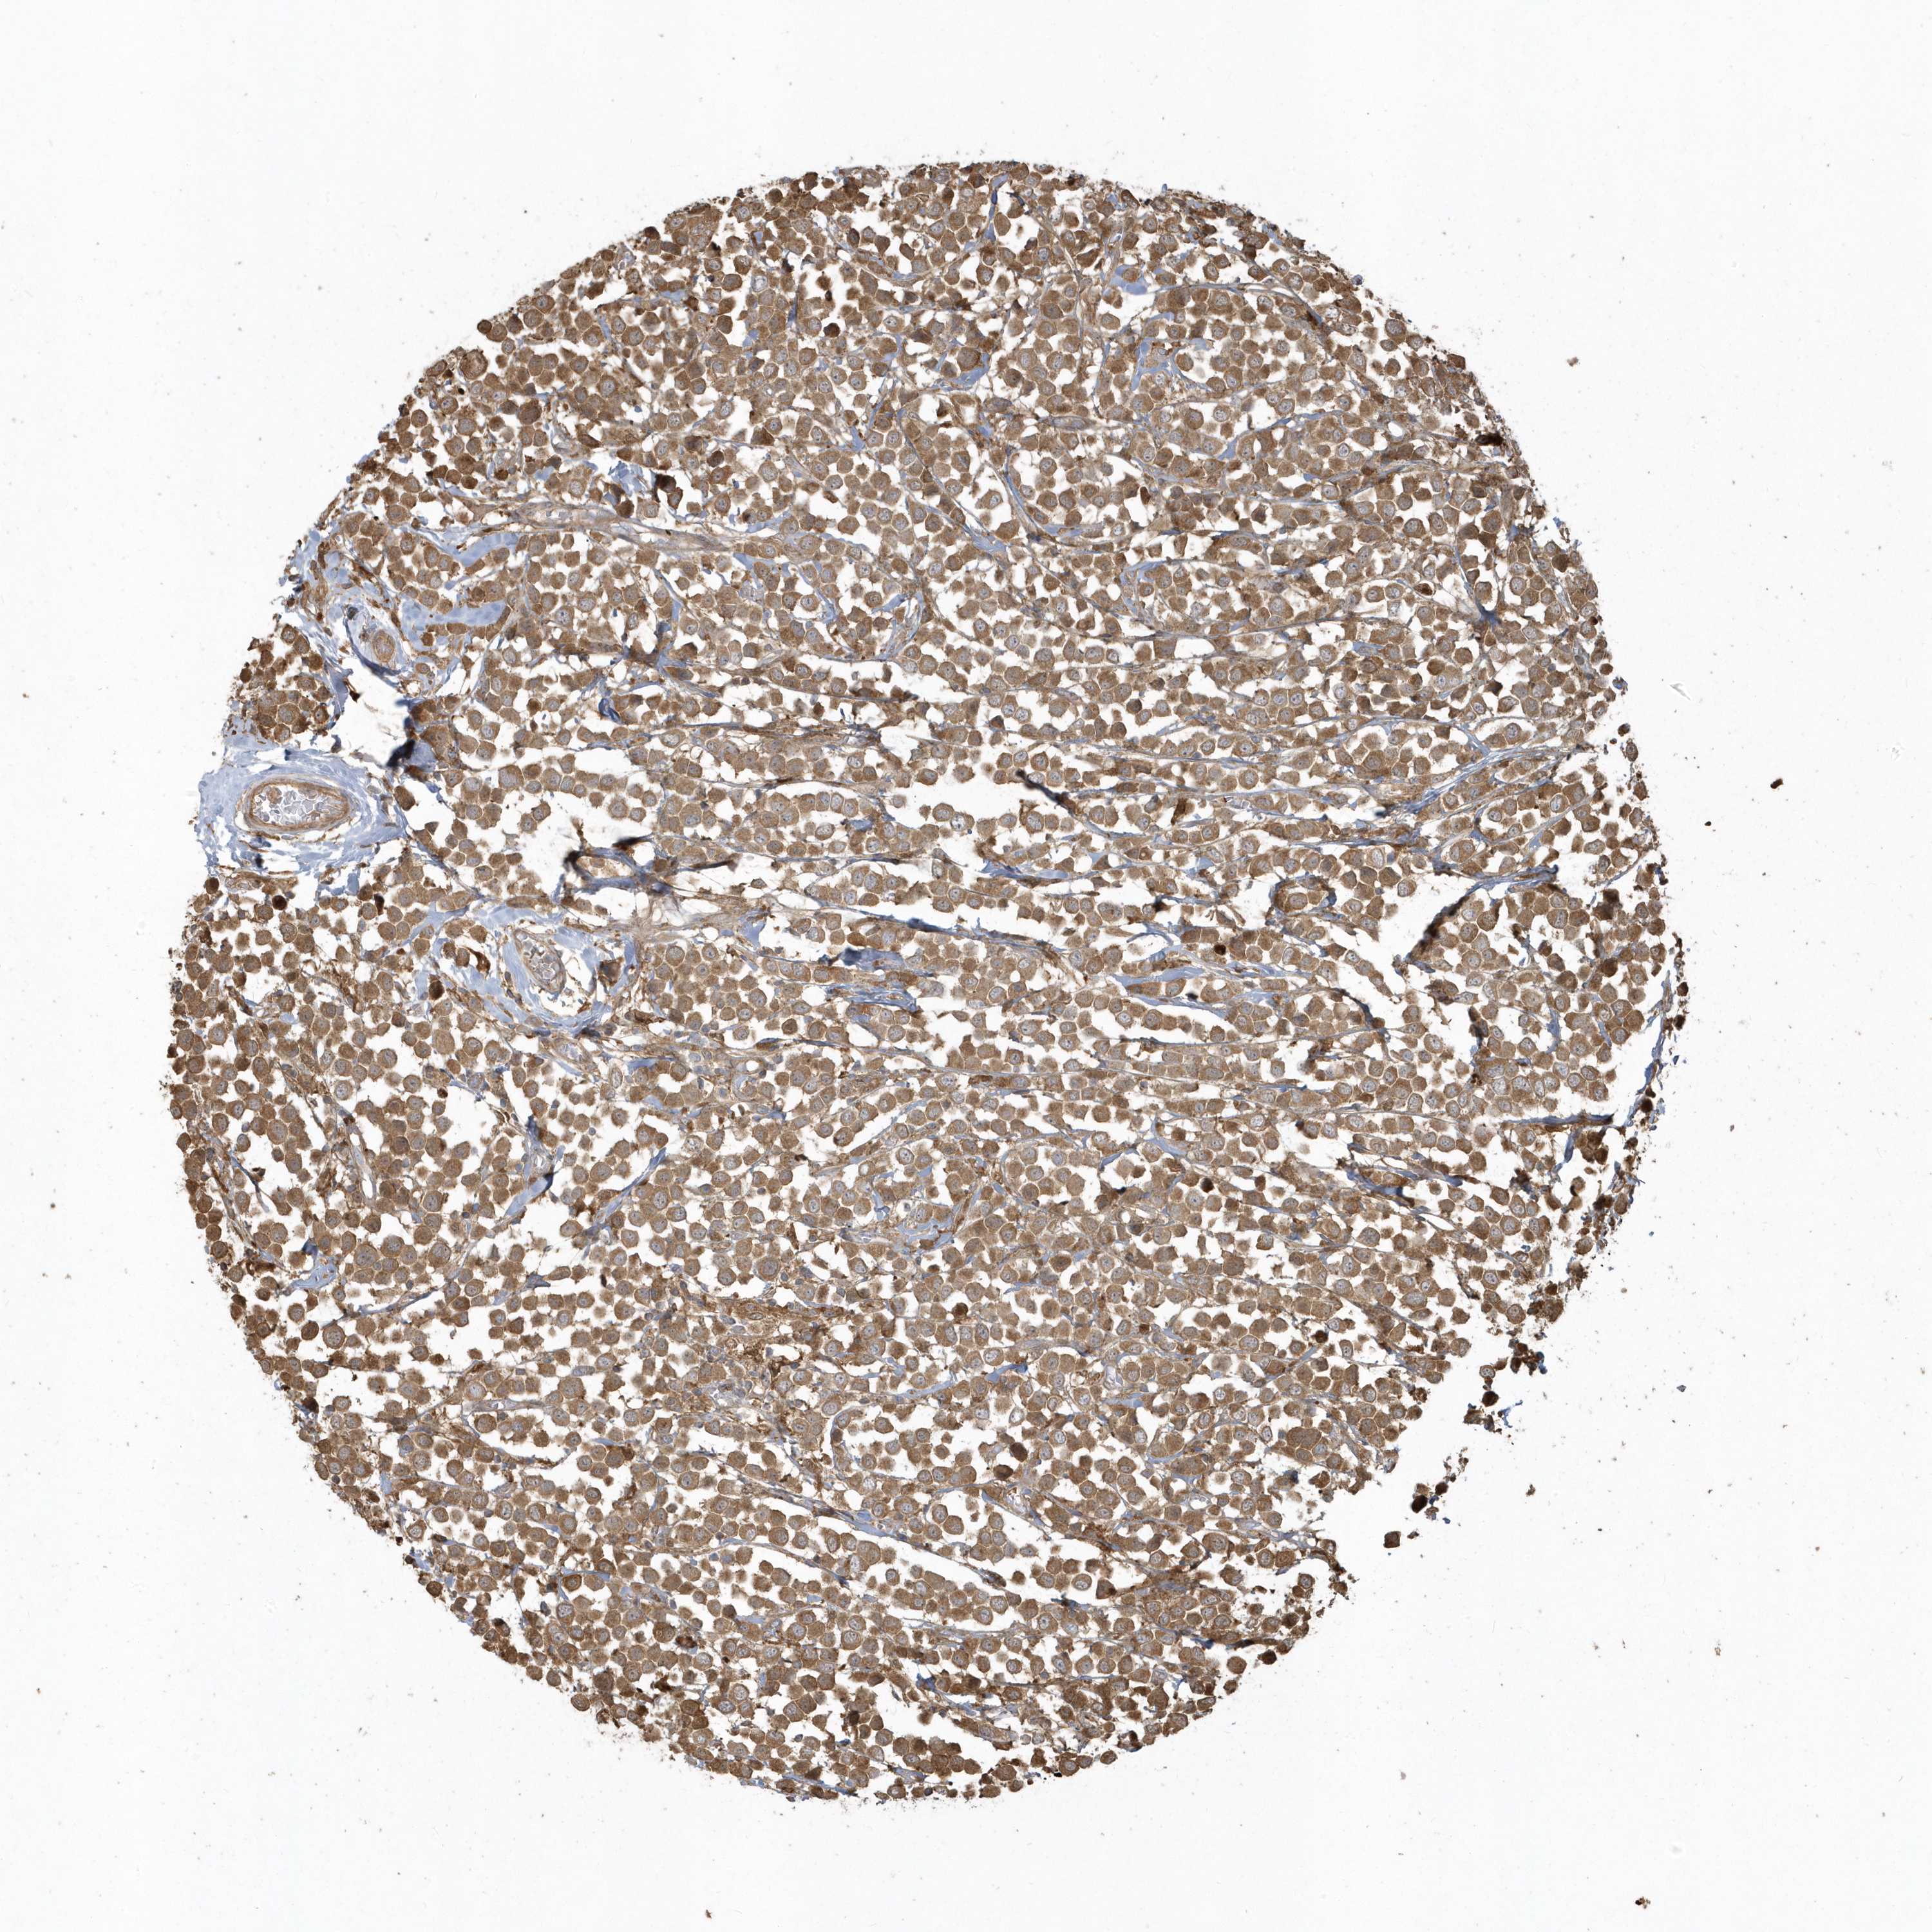

BRCA TCGA BRCA VALIDATION PROTEIN EXPRESSION

ANTIBODIES

AND

VALIDATION